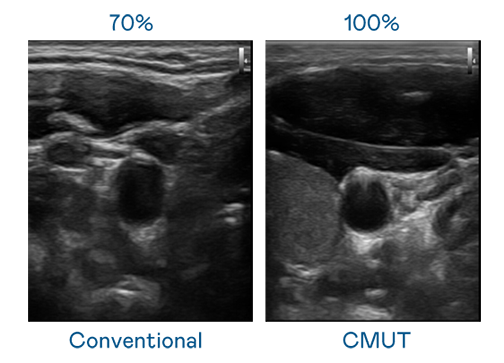

CMUT 技术是一种用电容式微机电元件来产生超音波讯号的技术。与传统 PZT 压电式技术相比,CMUT 频宽增加 30%,更宽频的超音波讯号让影像解析度大幅提升,是实现高影像品质医疗超音波扫描、促进精准医疗发展的关键技术。

大频宽带来超清晰影像

超音波影像的解析度高低,首先取决于探头能发出的讯号频宽。ag尊龙 CMUT 可提供高清晰的超音波讯号,提供高频宽、高灵敏度、影像纹理细节更高的超音波影像,协助医护人员缩短影像判读时间及利用精准的医疗影像进行诊断。